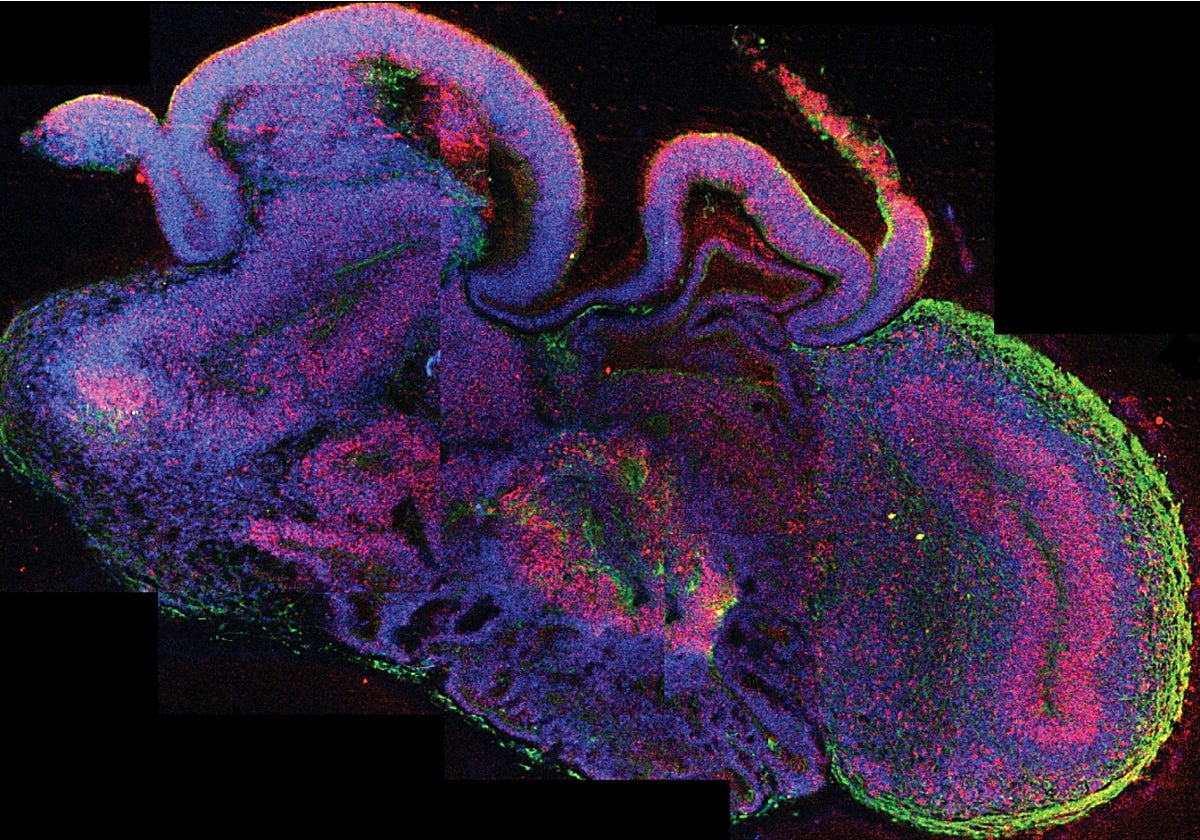

En 2011, el equipo de Sergiu Pașca, de la Universidad Stanford Medicine (EE.UU.) comenzó a desarrollar un método tridimensional para superar las limitaciones del cultivo bidimensional, dando lugar a los organoides cerebrales, que reproducen parte de la estructura cerebral humana. Estos organoides permiten observar el desarrollo cerebral humano en tiempo real durante varios años.

Más tarde, Pasca y su equipo crearon assembloides, fusionando organoides para imitar las conexiones neuronales naturales. Descubrieron que en los assembloides derivados del síndrome de Timothy, las interneuronas migratorias presentaban anomalías, lo que afectaba la señalización cerebral. En 2022, Pasca trasplantó organoides corticales humanos en ratas neonatales, observando la integración exitosa de neuronas humanas en el cerebro de las ratas, lo que podría tener implicaciones para el estudio y tratamiento de enfermedades neuropsiquiátricas.

Ahora, gracias a los organoides cerebrales (tejido cerebral tridimensional derivado de células madre humanas) se pueden probar intervenciones que apunten a tipos de células específicas afectadas en ciertas enfermedades, ya que son buenos para replicar enfermedades y predecir las respuestas humanas al tratamiento y, por lo tanto, pueden permitir desarrollar terapias efectivas.